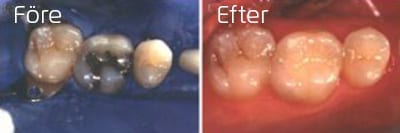

Porslinsonlay

Amalgamfyllning på sexårstanden ersätt med porslinsfyllning, s.k porslinsonlay